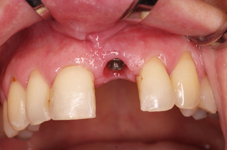

Klasickým příkladem a indikací pro použití implantátu je ztráta jednoho zubu (v tomto případě v předním – frontálním úseku) v jinak zdravém, nepoškozeném chrupu.

Nejčastější příčinou takové ztráty je sportovní nebo dopravní úraz.

Náhrada jednoho zubu pomocí implantátu je možná také v postranním úseku chrupu. Při ztrátě většího počtu zubů ve frontálním nebo postranním úseku může být mezer uzavřena větším počtem jednotlivých implantátů.

Při ošetření pomocí jednotlivých implantátů zůstávají sousední zuby neporušené – intaktní. Při klasickém ošetření pomocí můstků musejí být tyto zuby obroušeny!